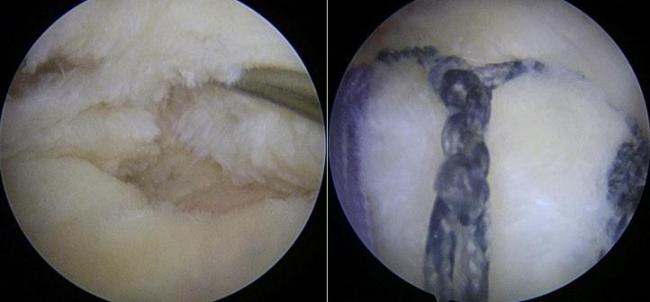

中国科大附一院骨科运动医学科亚专科主任赵其纯教授团队提出了一种创新的“Y-Loop”双排肩袖修补技术,并发表于国际期刊《Arthroscopy Techniques》。该技术以仿生、牢固、简便为核心优势,为肩袖修补提供了新的解决方案。

传统缝合方式力量集中在几个点上,容易切割退变的肌腱。而Y-Loop技术通过独特的套索环绕加外排固定方法,将内排锚钉的多根缝线连接成一个连续的整体网络,模拟了肩袖内的天然应力带结构,使牵拉力均匀分布到整个肌腱接触面,降低了缝线对脆弱肌腱的切割风险,为腱-骨愈合提供了更稳定的环境。

Y-Loop技术具有多项优势:生物力学更优,形成抗撕裂的横向锁定系统,提供强大的初始固定;减少线结对肩袖的横向牵拉,减轻外排固定对肌腱的纵向切割,减小对肌腱血供的影响,利于生物学愈合;仅需在经典双排技术上增加两个套索步骤,学习曲线短,易于推广;无需特殊耗材,使用常规锚钉即可完成手术,不额外增加患者经济负担。